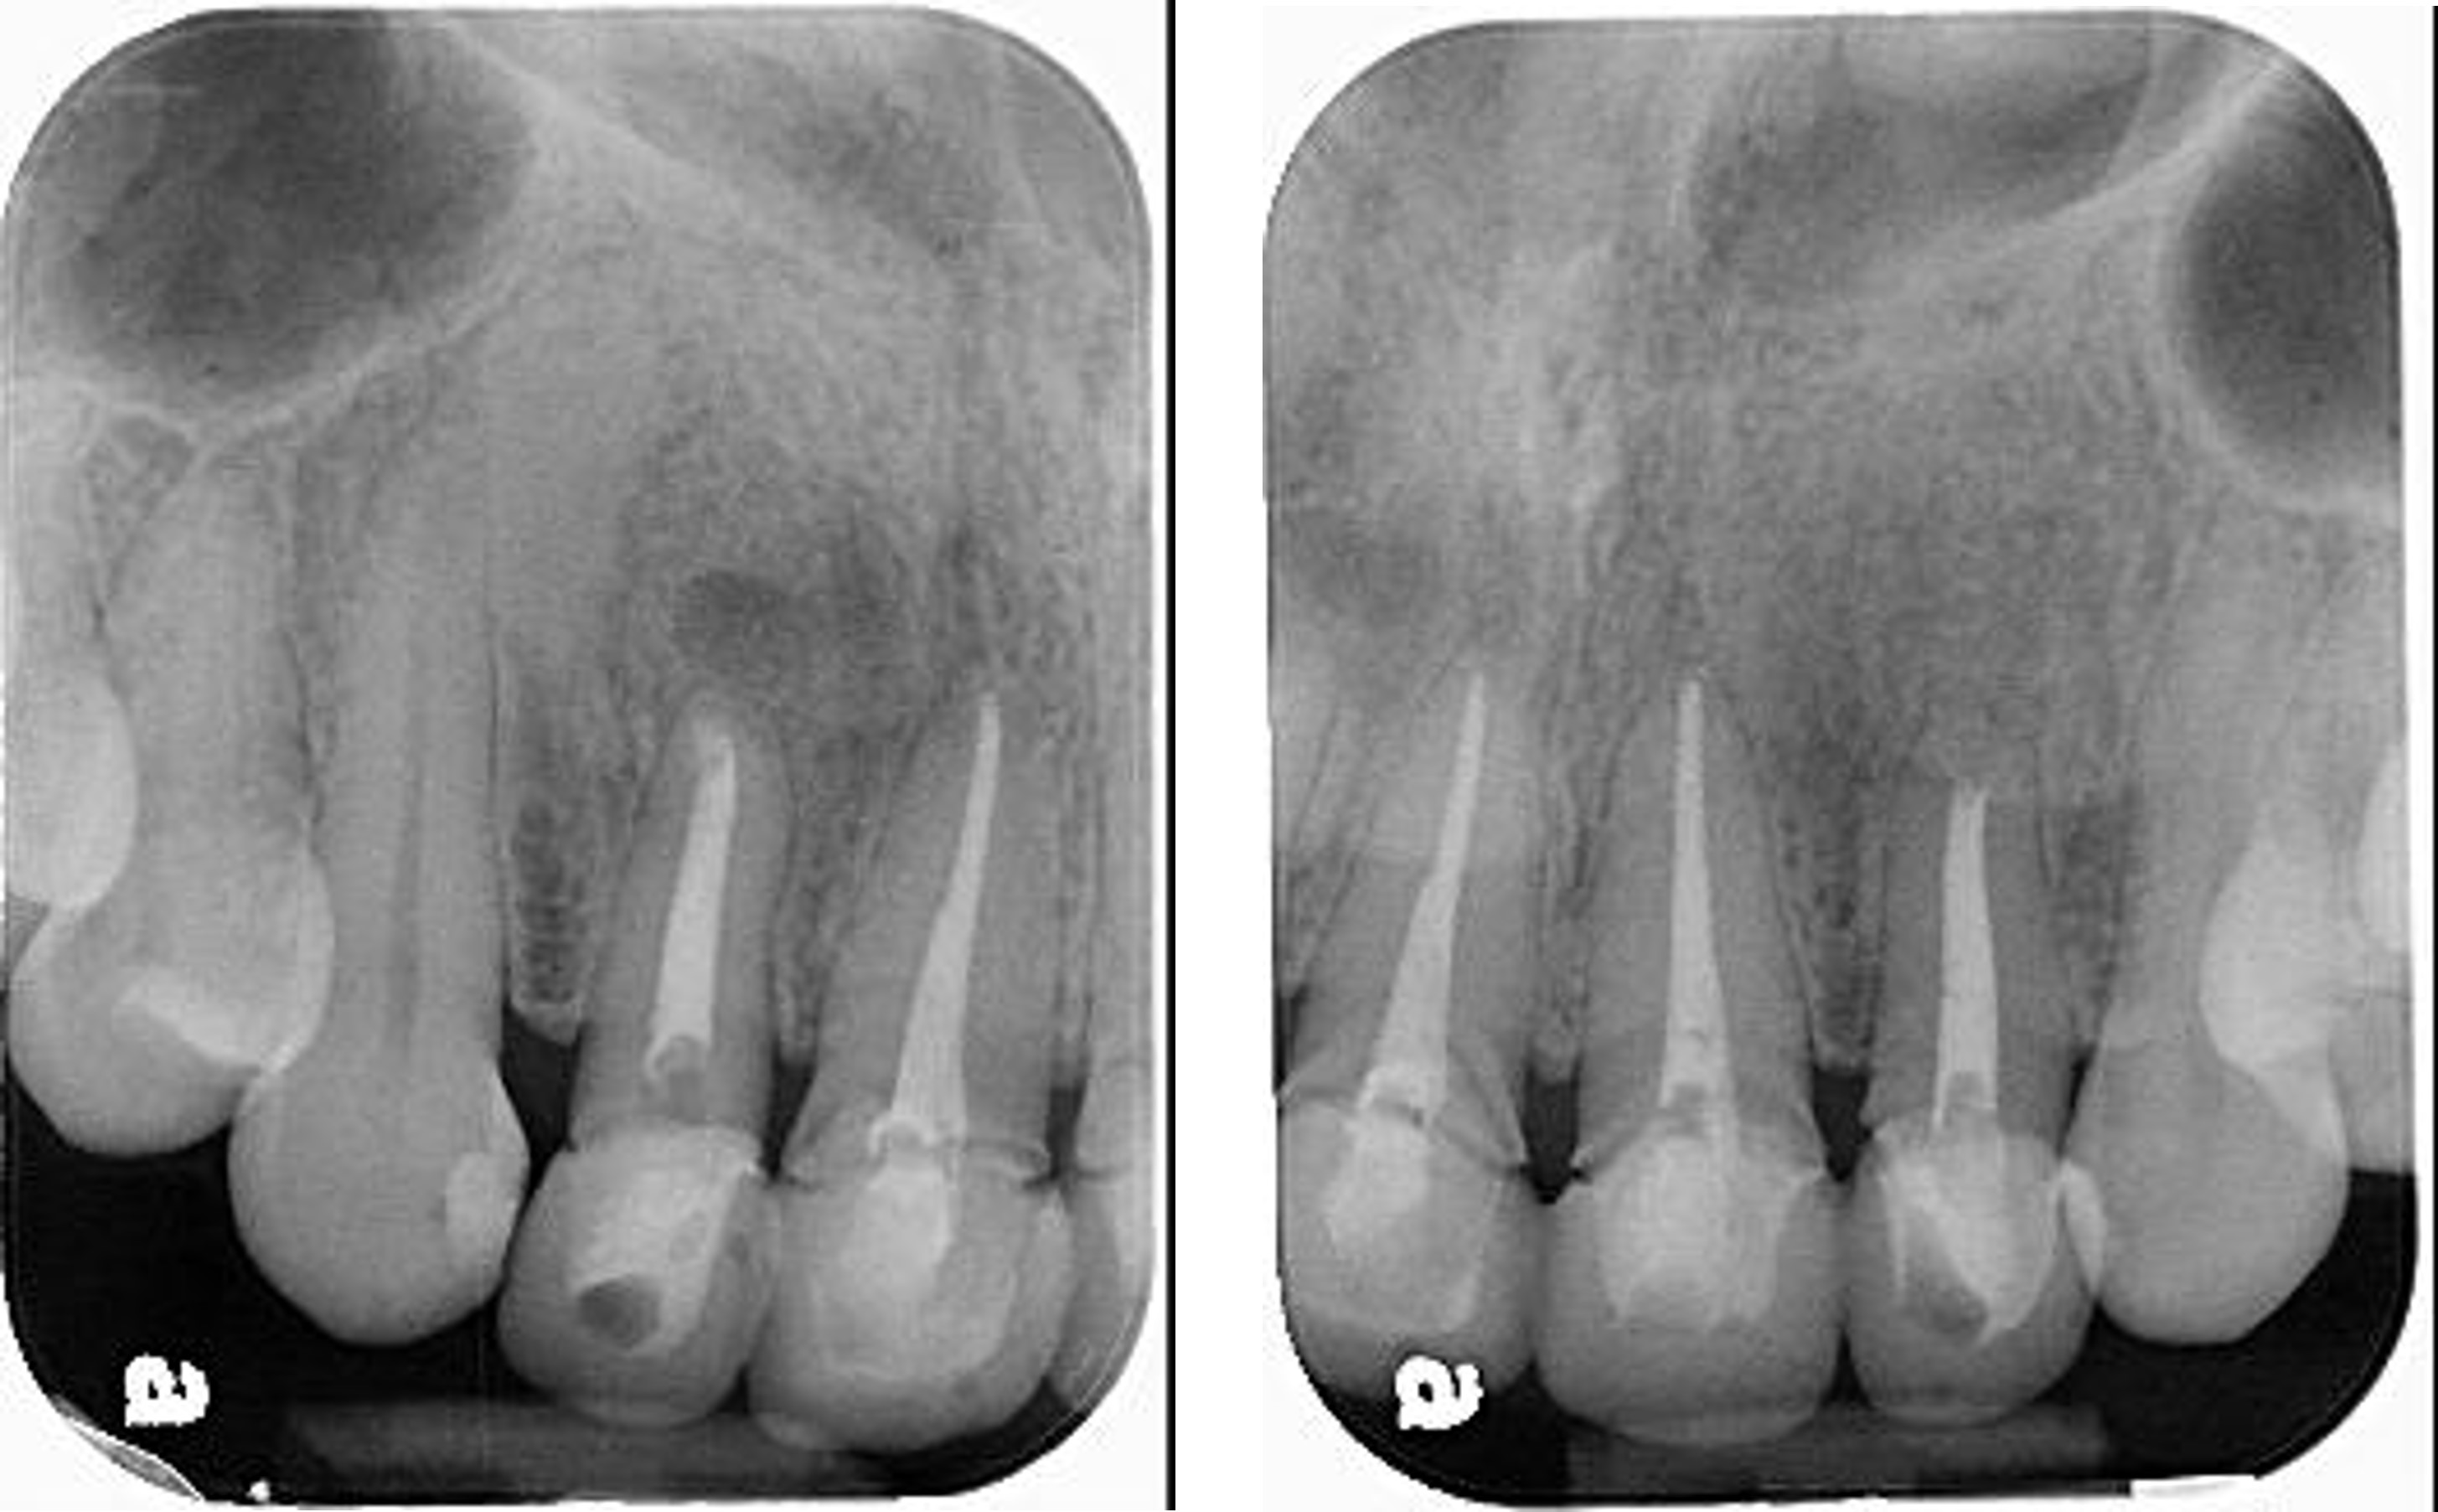

治療前,前牙病變,阻生齒等

治療前,前牙根管治療不完全

根管治療6個月後,仍有根尖病變

6個月後病變逐漸恢復

再6個月後,病變更消失